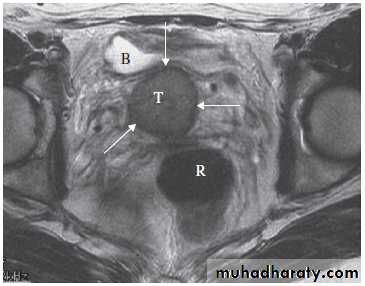

Magnetic resonance imaging is useful to determine the extent of carcinoma of the cervix preoperatively, because the extent (or tumour stage) determines whether the patient is managed with surgery or with chemoradiotherapy.

The observations to be made are whether the tumour is confined to the cervix .

It extends into the parametrium, lymph nodes, rectum, bladder or pelvic side walls .